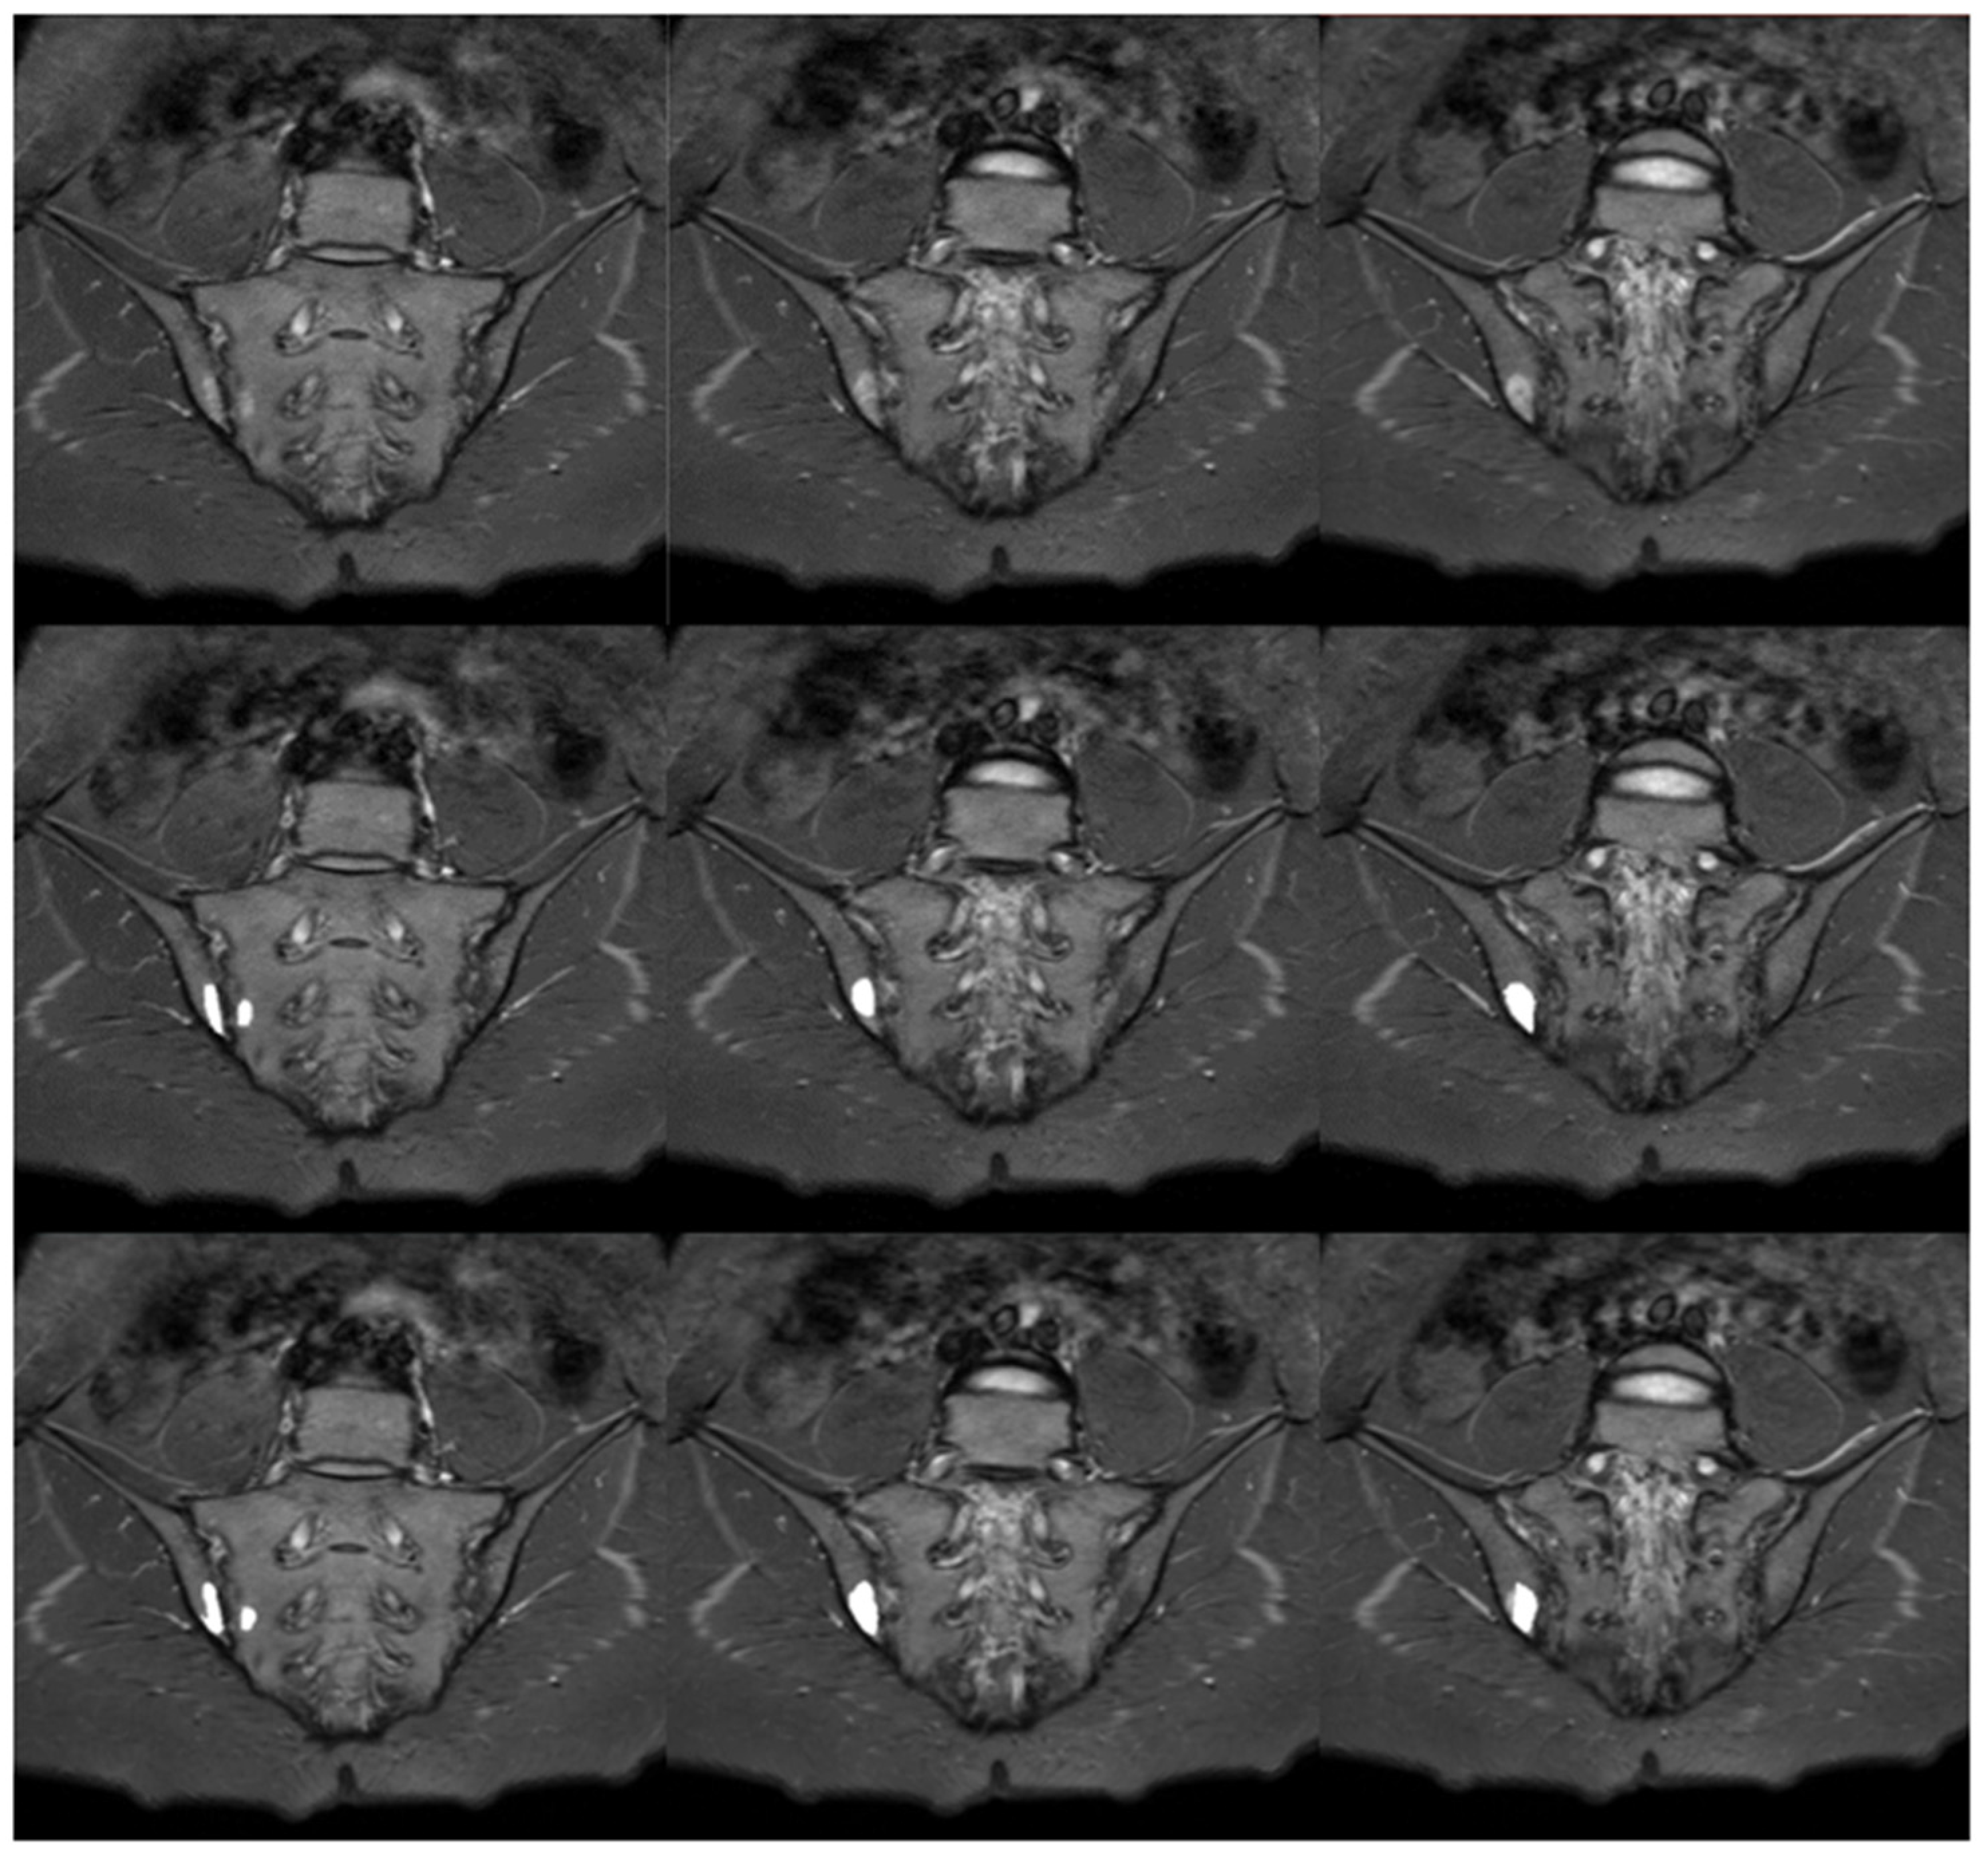

Figure 8.

Sample slices with inflammatory lesions (SPARCC = 17): STIR sequence in the upper row, manual segmentation in the middle row and automated segmentation in the lower row.

The sample comparison of the performance of manual and automatic segmentations of BME is presented in Figure 8. The results of assessing the compatibility of manual and automatic BME segmentations with the visual scale described previously are provided in Table 4. Differences between the groups were checked using Kruskal–Wallis H test, which resulted in not being statistically significant, H(3) = 1.125, p = 0.7710. This outcome implies no difference in the algorithm’s performance in BME segmentation in relationship to the deviation angle. Due to the limitations of the SPARCC scale, the number of examinations which points were awarded (SPARCC > 0, n = 68) differs from the number of examinations with BME recognized when preparing manual segmentations (n = 83).